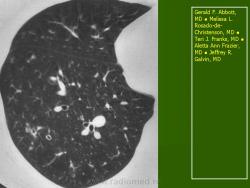

В 5 наблюдениях (21%) из больных с распространенной формой заболевания отмечались изменения в легких в виде обогащения, избыточности легочного рисунка, его деформации по сетчато-петлистому типу, очаговых теней. Корневая и медиастинальная аденопатия отсутствовали. В 1 случае в легких выявлена киста, которая периодически осложнялась нагноением (Рис. 4).

Поражение легочной ткани (рис. 22) свойственно любому возрасту. Часто больные имеют общие симптомы — лихорадку, слабость, реже — кашель, одышку, боли в грудной клетке. На рентгенограммах отмечается деформация и усиление легочного рисунка и микроузловые инфильтративные тени. Поражение костного мозга (с наличием клеток Лангерганса) сопровождается цитопенией периферической крови.

Рис. 22. Поражение легких при Лангер-гансово-клеточном гистиоцитозе.